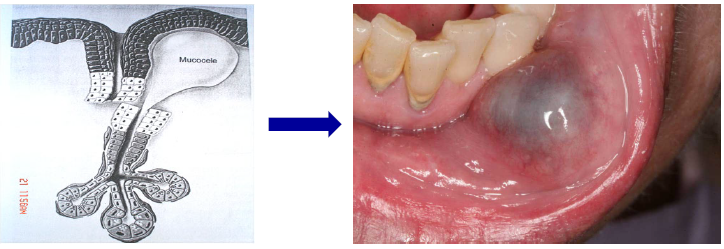

mucous extravasation phenomenon (mucocele)

mucous spillage into the soft tissues due to rupture of a minor salivary gland duct

causes by local trauma (common in kids)

fluid-filled lesions that is often blue or translucent in color

lower lip is the most common location